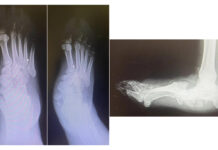

In alcuni casi selezionati, se si sospetta la presenza di osteomielite, sarebbe opportuno prescrivere anche una RM.

«Il rischio connesso alla diagnosi tardiva è il danno locale della cartilagine articolare, la necrosi ossea articolare ma anche alterazioni irreversibili o parzialmente reversibili della cartilagine di accrescimento», aggiunge Gigante. «Un’anca sede di una pregressa artrite settica non appropriatamente o tardivamente trattata può esitare non solo in una testa necrotica deforme ma anche in un collo femorale accorciato. Un insieme di alterazioni morfologiche che nel loro complesso espongono il paziente da adulto alla necessità di una protesizzazione totale dell’anca».

Soprattutto quando l’infezione è a carico dell’anca, infatti, occorre effettuare una «evacuazione chirurgica. Già dopo 8 ore gli enzimi proteolitici liberati dalle cellule infiammatorie producono un danno istologico delle cartilagini.

Un secondo meccanismo con cui si produce un danno a livello dell’anca è l’aumento della pressione articolare che interferisce con la vascolarizzazione e se non c’è ossigeno che perviene alle cellule epifisarie si ha un infarto della testa e quindi alterazioni di tipo distruttivo che possono essere anche irreversibili.